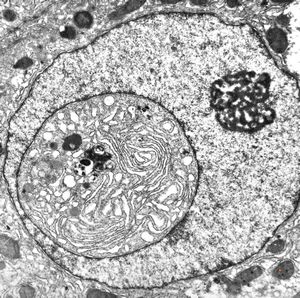

M,3y. | normal hepatocyte

M,19y. | normal hepatocyte

M,2y. | normal hepatocyte

normal hepatocyte